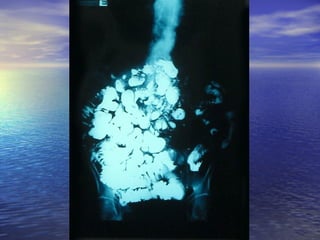

• Estudio radiológico consiste enEstudio radiológico consiste en

administración de 250ml oral de bario y laadministración de 250ml oral de bario y la

obtención de radiografías seriadas delobtención de radiografías seriadas del

intestino, realizadas a intervalos, hastaintestino, realizadas a intervalos, hasta

que el contraste llega al cielo.que el contraste llega al cielo.

Transito intestinalTransito intestinal Definición:Definición: •Estudio radiológico consiste enEstudio radiológico consiste en administración de 250ml oral de bario y laadministración de 250ml oral de bario y la obtención de radiografías seriadas delobtención de radiografías seriadas del intestino, realizadas a intervalos, hastaintestino, realizadas a intervalos, hasta que el contraste llega al cielo.que el contraste llega al cielo.